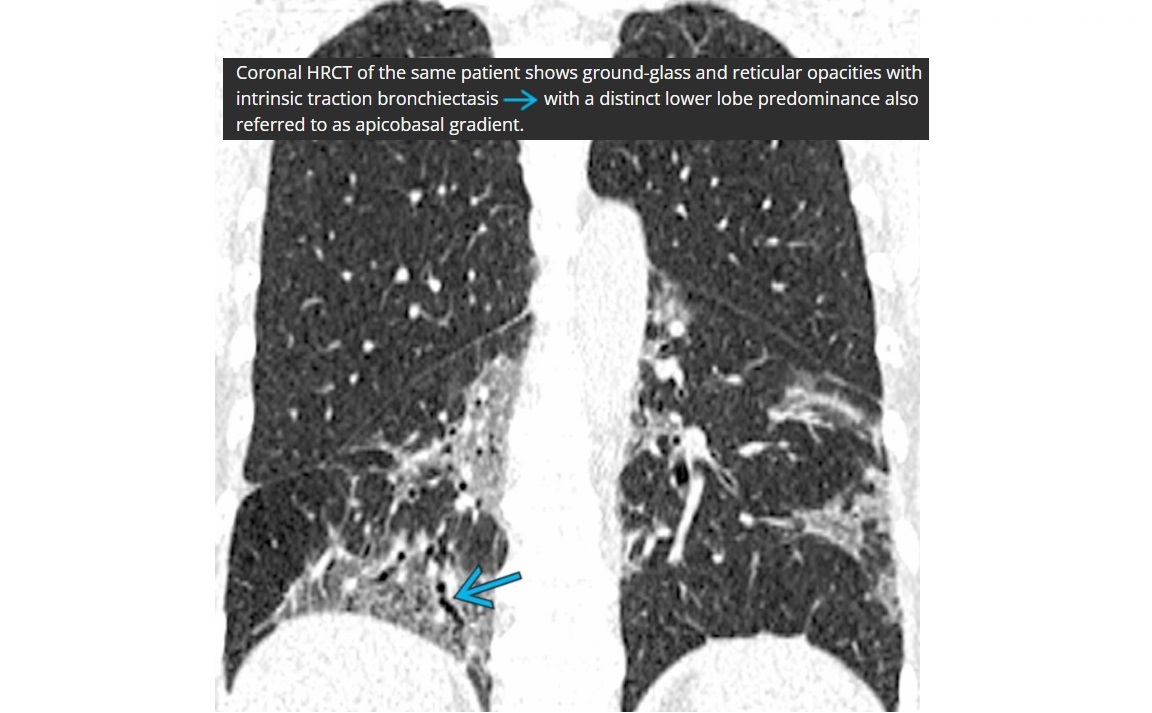

NSIP

lower lung zone predominant

CXR

bilateral, reticular opacities

CT

Absent (less) / microcystic honeycombing

Bilateral ground-glass &/or reticular opacities

Traction bronchiectasis/bronchiolectasis

Relative Subpleural sparing

peribronchovascular fibrosis

Most hunt for assocation/cause on CT

?dilated oesophagus - scleroderma

? joint disease - RA

?portcath/PICC - chemotherapy

sjorgens

HIV